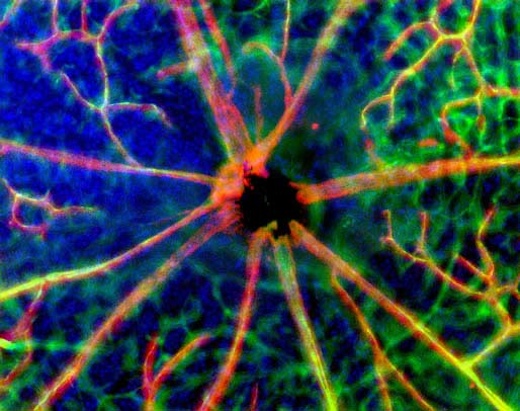

Per verificare la loro ipotesi i ricercatori hanno usato topi emicranici e con un tracciante colorato iniettato negli occhi di questi ultimi hanno seguito il percorso naturale dai fotorecettori melanopsinici al cervello. Così hanno visto che la ‘strada della luce’ porta fino a una famiglia di neuroni che si attiva proprio durante l’attacco emicranico